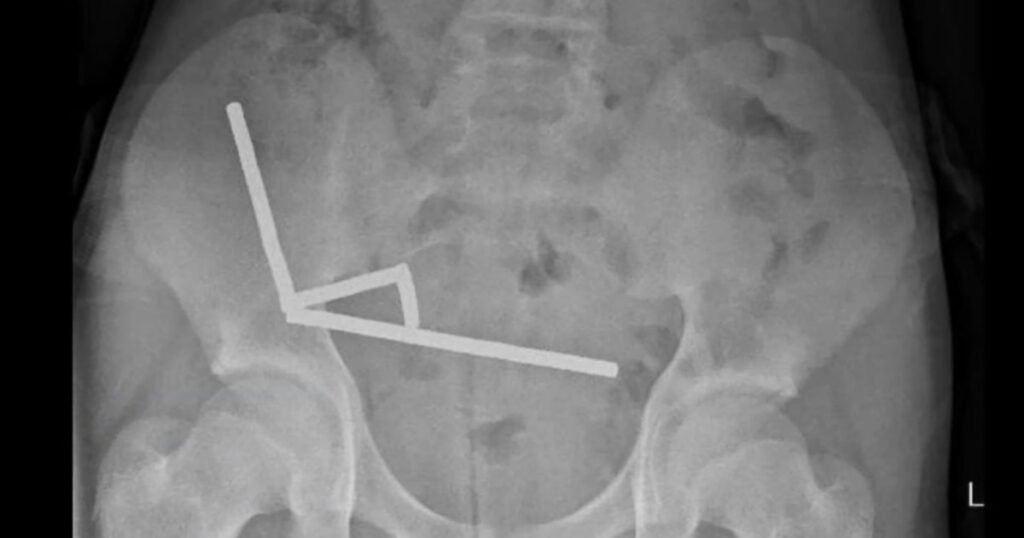

After four days of stomach pain, the 13-year-old boy was admitted to Tauranga Hospital on New Zealand’s North Island, where doctors discovered the magnets had joined together to form four chains inside his intestines.

Surgeons extracted the magnets and removed parts of the boy’s damaged intestines, according to a report by doctors at the hospital, published Friday in the New Zealand Medical Journal.

The boy, who was not identified in the report, had swallowed “approximately 80–100 5x2mm high-power neodymium magnets” a week prior to his hospitalization, the doctors said. He was discharged after spending eight days in the hospital.